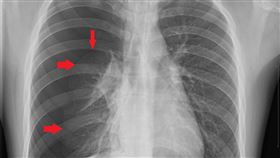

高中生打籃球突胸痛 竟是自發性氣胸

小明是一位身材高瘦的高中生,平時熱愛籃球運動。日前在...

2021/03/08 09:29